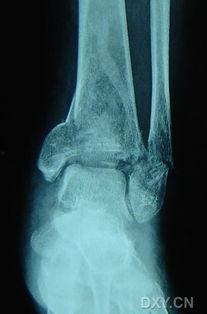

首先,让我们来了解一下脚踝骨折。脚踝骨折是一种常见的运动损伤,通常发生在脚踝扭伤后。当脚踝承受过大的压力或扭曲时,骨骼可能会断裂。这种损伤可能会导致疼痛、肿胀和活动受限。